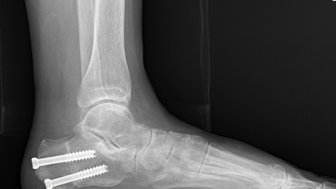

PTTD, ankle

Calcaneal medialization osteotomy + FDL tendon transfer, Lt Under the spinal anesthesia, the p...